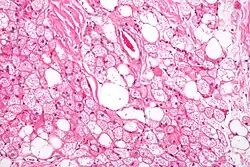

Micrograph of a hibernoma. H&E stain. | |

The tumors histologically resemble brown fat. There are four histologic types recognized, but one is the most frequently seen (typical). There is a background of rich vascularity.

- Lobular type: Variable degrees of differentiation of uniform, round to oval cells with granular eosinophilic cells with prominent borders, alternating with coarsely multivacuolated fat cells (pale cells). There are usually small centrally placed nuclei without pleomorphism. The cells have large cytoplasmic lipid droplets interspersed throughout.[4][5]

- Myxoid variant: Loose, basophilic matrix, with thick fibrous septa, and foamy histiocytes

- Lipoma-like variant: Univacuolated lipocytes, with only isolated hibernoma cells

- Spindle cell variant: Spindle cell lipoma combined with hibernoma